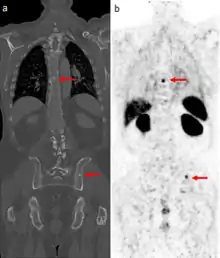

The main (67Ga) technique uses scintigraphy to produce two-dimensional images. After the tracer has been injected, images are typically taken by a gamma camera at 24, 48, and in some cases, 72, and 96 hours later.[23][24] Each set of images takes 30–60 minutes, depending on the size of the area being imaged. The resulting image will have bright areas that collected large amounts of tracer, because inflammation is present or rapid cell division is occurring. Single-photon emission computed tomography (SPECT) images may also be acquired. In some imaging centers, SPECT images may be combined with computed tomography (CT) scan using either fusion software or SPECT/CT hybrid cameras to superimpose both physiological image-information from the gallium scan, and anatomical information from the CT scan.

Gallium DOTA scans

68Ga DOTA conjugated peptides (including 68Ga DOTA-TATE, DOTA-TOC and DOTA-NOC) are used in positron emission tomography (PET) imaging of neuroendocrine tumours (NETs). The scan is similar to the SPECT octreotide scan in that an octreotide-based somatostatin analogue (such as edotreotide) is used as the radioligand, and there are similar indications and uses as ocreotide scans, however image quality is significantly improved.[35] Somatostatin receptors are overexpressed in many NETs, so that the 68Ga DOTA conjugated peptide is preferentially taken up in these locations, and visualised on the scan.[36] As well as diagnosis and staging of NETs, 68Ga DOTA conjugated peptide imaging may be used for planning and dosimetry in preparation for lutetium-177 or yttrium-90 DOTA therapy.[37][38]